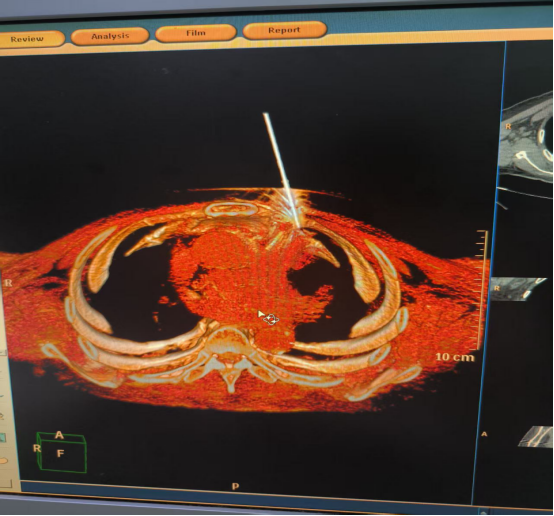

1. 精准定位的“狙击手”模式

CT影像能够提供毫米级的精准定位。尤其是对于深部小病灶(如早期肺部小结节),CT引导可以帮助医生一次性准确到达,避免“盲穿”多次尝试的风险。

CT扫描能够实时显示手术路径上的重要血管、神经和器官,自动预警危险区域,就像行车导航会提醒前方有障碍物一样。医生可以随时调整方案,选择最安全的路径,大幅降低手术风险。